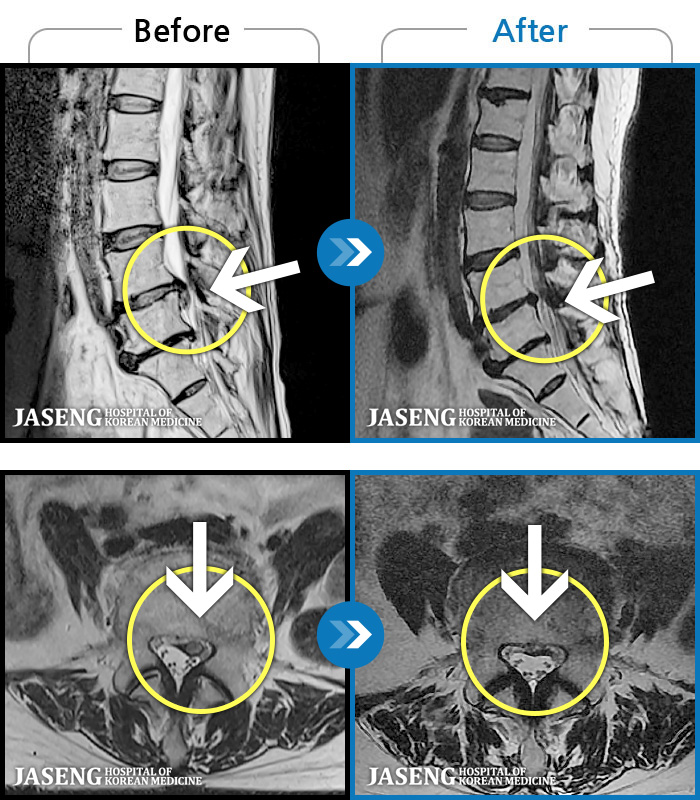

MRI ũ ʸ Ȯϼ.

[뱸] 19.11.28~25.05.06